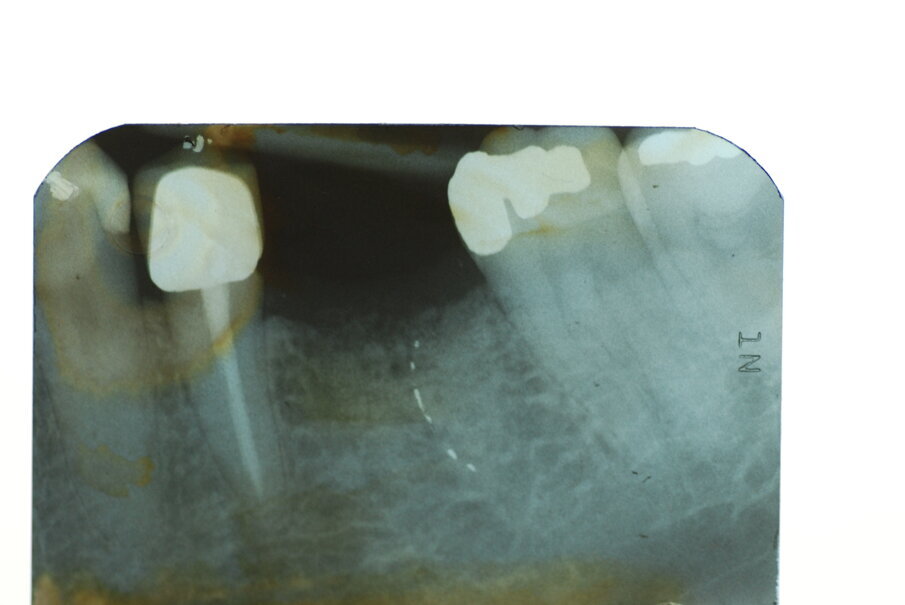

I lembi sono stati poi suturati a livello dell’osso (Gore-Tex®, 4.0, Gore, Newark/ NJ, USA) senza la necessità di ottenere una chiusura completa (Fig. 3). In fase postoperatoria è stato prescritto un antinfiammatorio (Nimesulide 100 mg, 2 volte al giorno per 3 giorni), un analgesico (Paracetamolo 500 mg, 1 compressa ogni 8 ore per 3 giorni) e clorexidina 0.12%, e fornita istruzione completa all’igiene orale. La sutura è stata rimossa dopo 10 giorni. A 3 e a 6 mesi sono state eseguite le radiografie periapicali parallele.

Le radiografie eseguite immediatamente dopo l’intervento chirurgico con la tecnica GBR hanno indicato che l’alveolo post-estrattivo era stato adeguatamente zeppato con granuli di osso bovino decellularizzato (Fig. 7). Il richiamo a 6 mesi, ha mostrato tessuti molli in buona salute senza la presenza di segni di infiammazione (Fig. 8). La radiografia periapicale ha mostrato la perfetta guarigione dell’alveolo post-estrattivo (Figg. 9, 10). Anche durante l’esposizione ossea per il posizionamento dell’impianto, l’osso appare in buona salute e non sono presenti granuli di biomateriale non integrato. La membrana di pericardio bovino è completamente riassorbita (Fig. 11).